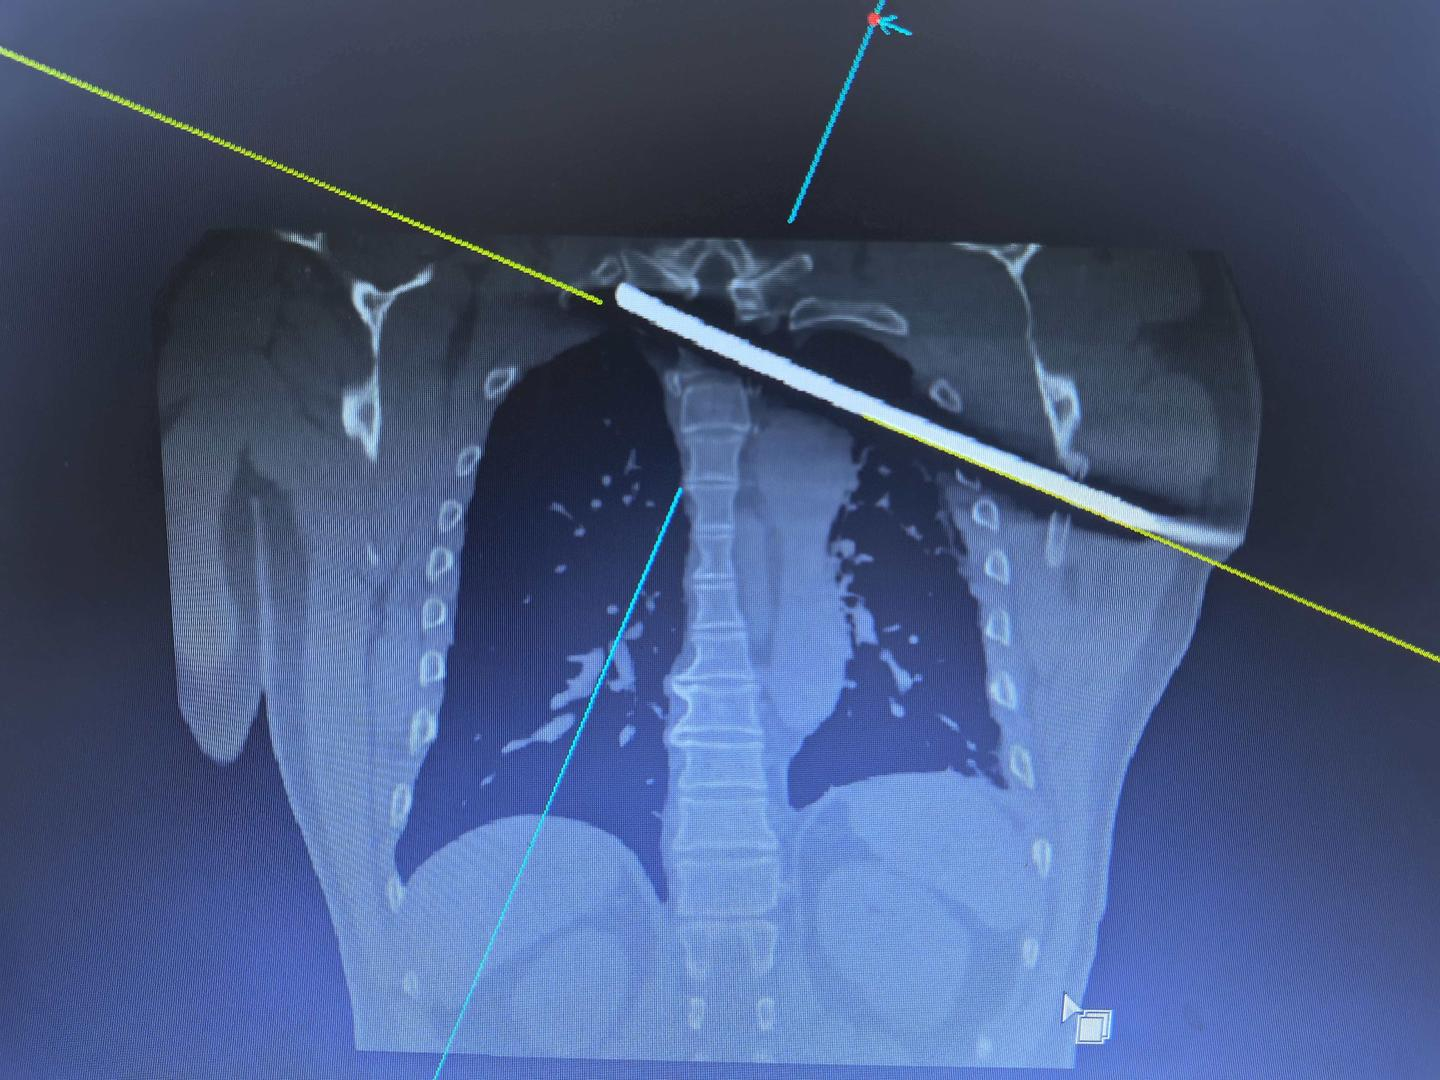

【30厘米钢筋插进胸腔直抵脊髓,6小时彻夜抢救!伤者:对身体的感知正在逐渐恢复】11月17日,四川省人民医院接诊了一名危重伤者,53岁的工人失足从4米高空坠落,被一根直径1厘米、长30厘米的钢筋,紧贴着心脏大动脉插进胸腔、直抵脊髓,生命危在旦夕。“18日凌晨1点开始手术,一直持续到第二天早上6时55分,钢筋被顺利取出,如今经过几天的康复,患者如今意识清醒,肢体感觉正在逐步恢复。”11月21日,医院骨科主任医师张伟表示,“脊柱脊髓受伤后的8小时内是最佳手术时机,我们医院专门为此设置了救治快速通道,希望借此能在保住患者生命的同时,尽可能让其更好的恢复、重返正常生活!”